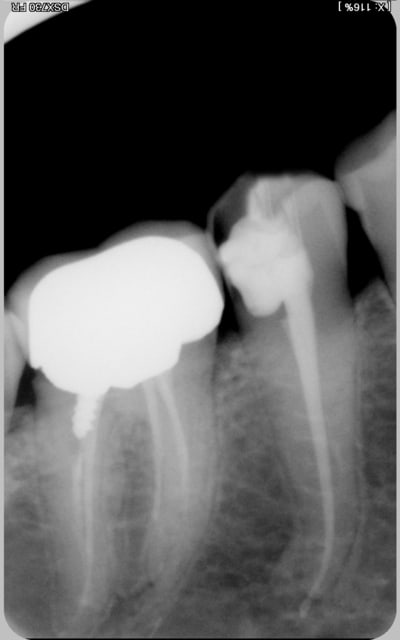

encore des radios,peut-etre assez moyen comme traitement...mais je vu pire...

les dernieres radios. patient en urgence ,abces... il voulait pas extraire la dent. j'ai lui bien explque et il a choisi de essayer de garder la dent. retrait,pas d'isolation avec la digue donc pas de tenon fibree,amalgam et screw post.traitement fait il ya 2 ans je crois.patient fidel de cabinet maintenent.

j'ai jamais utilise en roumanie l'amalgam et ca s'utilise pas du tout dans le cabinet du roumanie.